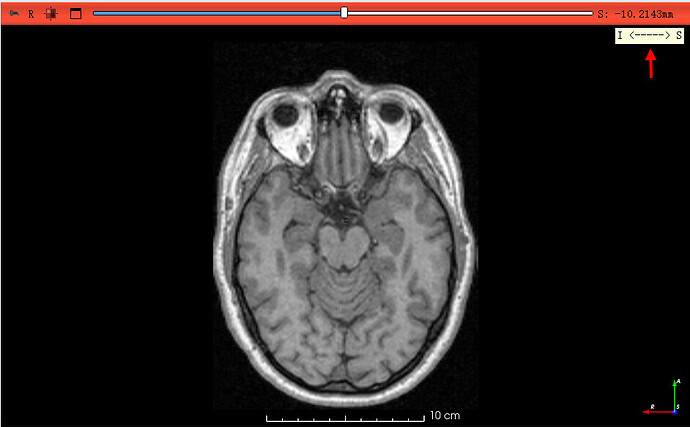

将Dicom格式转化为Nifit后,发现图片前后方向反了,请问怎样在3d-slicer中把图片方向调整过来,看了论坛中几个类似的贴,但是,还是没有明白要怎么操作,请求指导!

二、在 3D Slicer 中查看方向是否反了

查看坐标轴标签

- 打开任意二维视窗(红/黄/绿视窗),右上角有小字母指示(例如

A–P、L–R、S–I)。 - 若发现“前后颠倒”,例如解剖明显朝向错误(脸部在后),说明 NIfTI 在 A/P 方向反了。